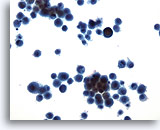

Pleural effusion:

Metastatic carcinoma of the breast.

10X

Pleural effusion:

Metastatic carcinoma of the breast.

20X

Figures 76-77: Pleural effusion: Metastatic carcinoma of the breast.

The classic description of metastatic breast cancer in pleural effusions employs the term “cannonballs” to emphasize the rounded arrangement of tumor cells. Note the relatively small nuclear size. Nuclei are vesicular with prominent nucleoli. Cytoplasmic vacuoles are uncommon. A cell block of the cells allows for assay of hormonal receptors or other epithelial markers, such as her-2-neu.